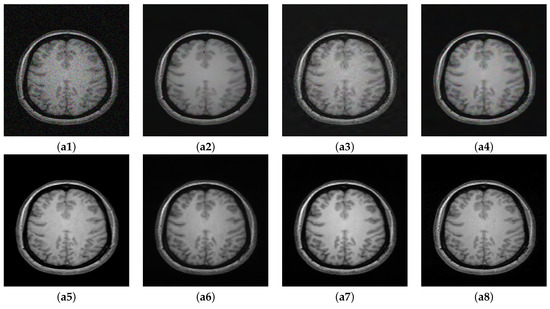

In this section, we summarize the discussion of our results. The results of Experiment I are shown in Figure 5, Figure 6 and Figure 7, where the denoising performance of the proposed method is shown in comparison with state-of-the-art denoising methods. In Figure 5, the input images were contaminated using 13% noise. All the images denoised using different approaches suppress noise to some extent; however, NLM [10] removes important structural details in the image and oversmoothes the contents of the denoised image during the restoration. Wavelet-based technique SURE [58] and BM3D [59] preserve the structural details; however, they do not eradicate noise to a reasonable extent. The deep learning methods clearly show better performance compared to the traditional methods, both in removing noise and maintaining the morphology of the image. Both MCDN [24] and FFD-Net [53] effectively remove the noise. Similarly, C M G D N e t also eradicates noise with reasonable preservation of the structural information. The enlarged ROIs are also shown in the figure for careful insight into the denoising performance of all the methods. Figure 6 shows the results of denoising applied on images contaminated with 8% noise. A similar trend can be observed in this case as well where the methods MCDN [24], FFD-Net [53], and C M G D N e t preserve important structures in the denoised images. However, NLM [10] produces over-smoothing effects. The performance was quantitatively evaluated using PSNR, SSIM, and FSIM. BM3D [59] works better compared to NLM and SURE [58]; this claim is also supported by the higher PSNR value in Table 2. The performance of FFD-Net [53] and MCDN is very similar when quantitatively evaluated. However, C M G D N e t performs best among all the techniques evaluated.

Figure 6. Denoising Results: Noise Level 8%. (a1) Noisy. (a2) NLM [10]. (a3) SURE [58]. (a4) BM3D [59]. (a5) MCDN [24]. (a6) FFD-Net [53]. (a7) C M G D N e t s g . (a8) GT.